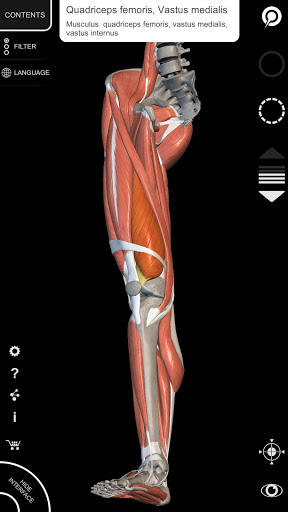

"Anatomy 3D Atlas" cho phép bạn nghiên cứu giải phẫu người theo cách dễ dàng và tương tác.

Thông qua giao diện đơn giản và trực quan, bạn có thể quan sát mọi cấu trúc giải phẫu từ mọi góc độ.

Các mô hình giải phẫu 3D đặc biệt chi tiết và có kết cấu lên đến độ phân giải 4k.

Việc phân chia theo vùng và chế độ xem được xác định trước giúp quan sát và nghiên cứu các bộ phận hoặc nhóm hệ thống riêng lẻ và mối quan hệ giữa các cơ quan khác nhau.

• Hệ thống cơ xương

• Xoay và phóng to từng mô hình trong không gian 3D

• Hình dung các cơ qua các lớp từ lớp nông đến lớp sâu nhất